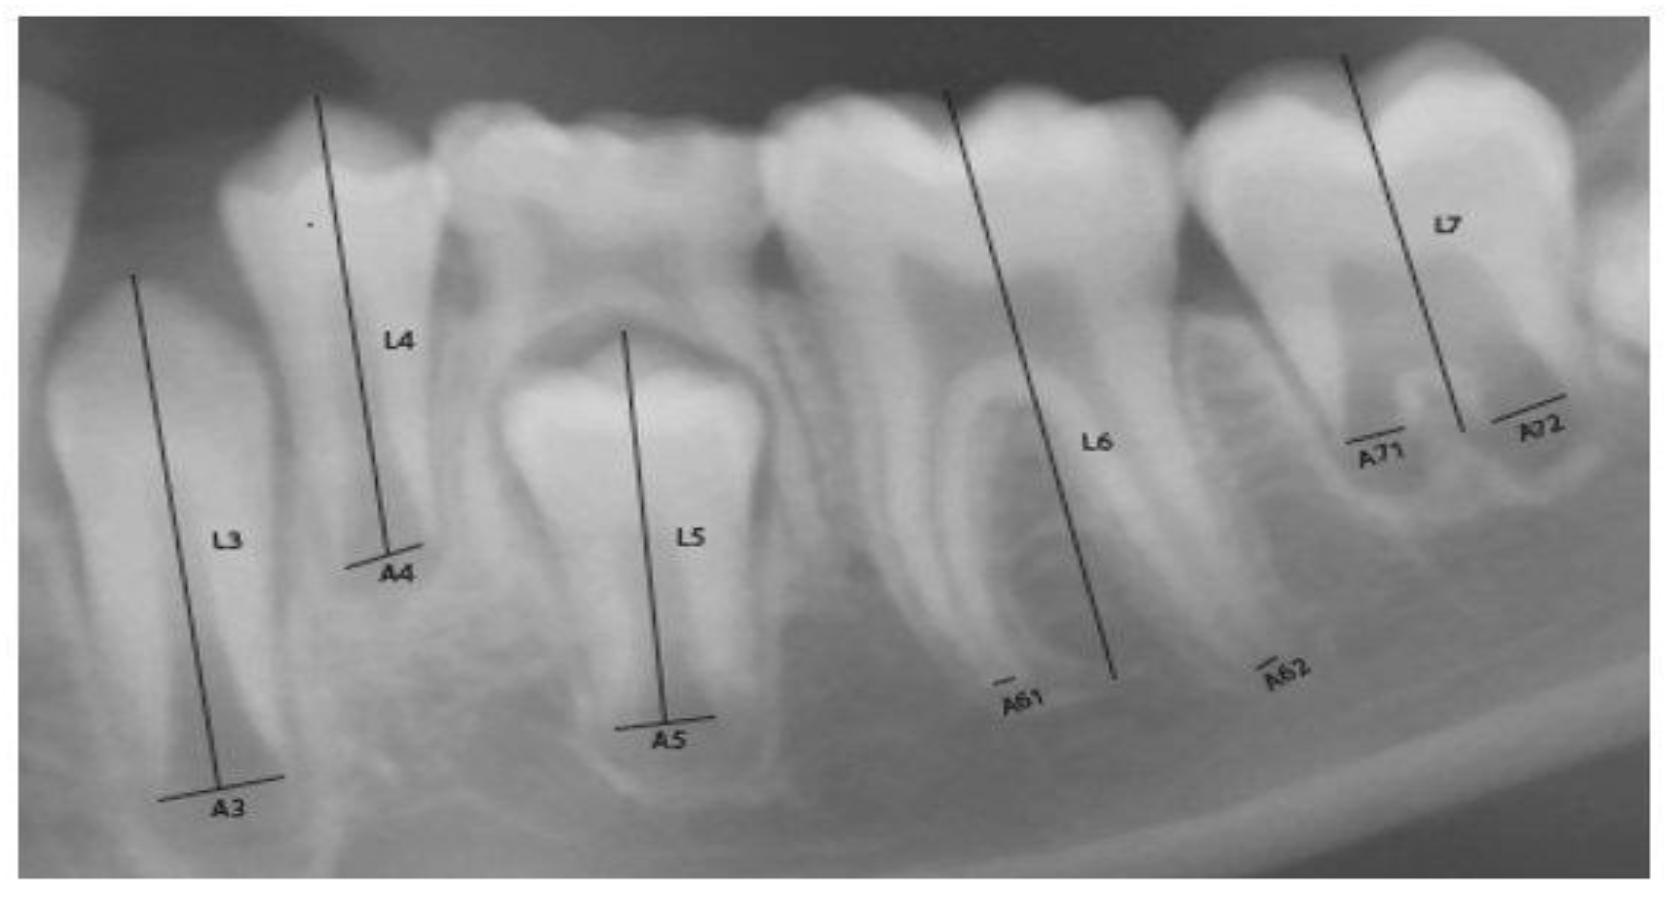

![]() |